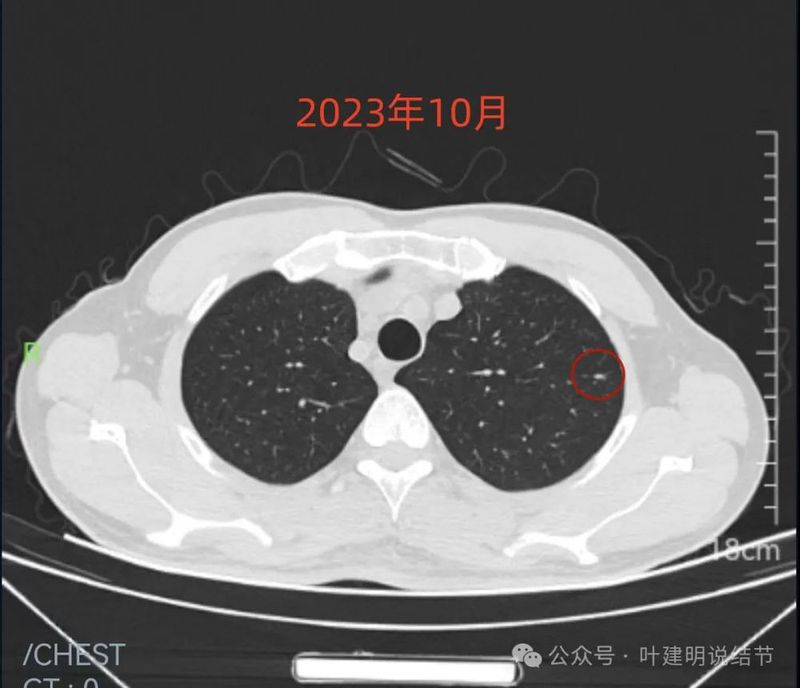

先看不同时间的明显层面截图:

2019年9月时右中叶磨玻璃密度病灶,轮廓与边界清楚,没有实性成分,中间密度稍低,考虑肿瘤范畴的,原位癌或微浸润性腺癌可能性较大。

2023年10月时右侧病灶没有明显进展。

红色的就是报告上所主要的病灶,右肺中叶的,这个病灶是磨玻璃结节,整体轮廓清楚,瘤肺边界也清,是要考虑是肿瘤范畴的。但是它密度低,没有实性成分,目前风险还不大,还没有到一定要干预的程度,或许在观察三年5年8年也不见得一定会进展。我的想法是再观察一下,半年到一年之间复查都可以。蓝色的界限欠清,实性部分密度过高,像炎性点。意见供参考!